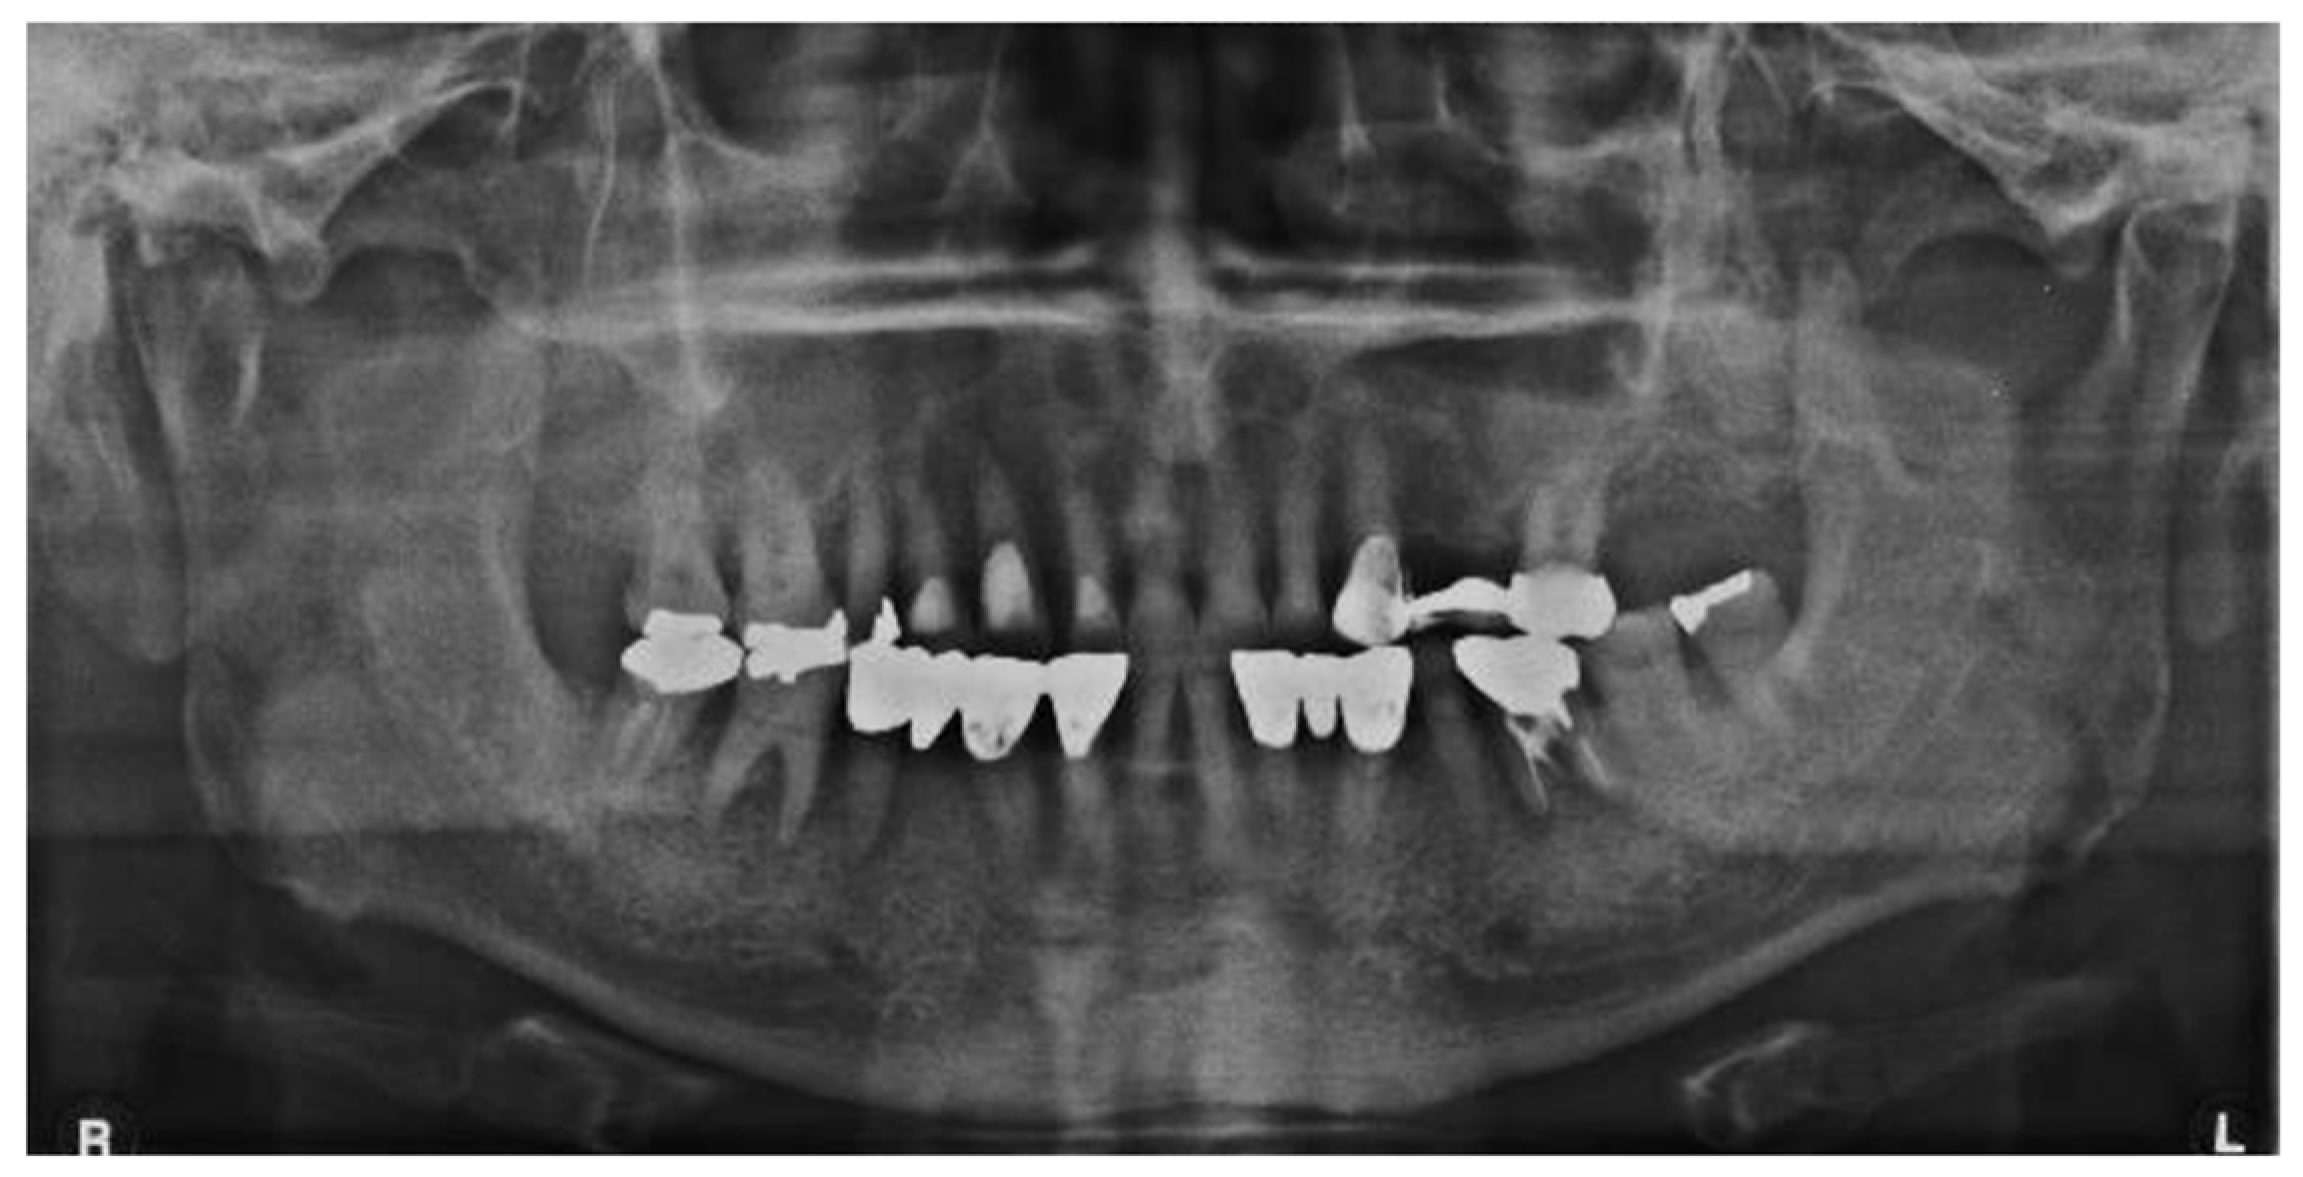

Panoramic radiographic findings were inconclusive for the presenting clinical symptoms (Figure 2). Computed tomography (CT) showed atrophy of the right masseter muscle, temporalis muscle, and lateral and medial pterygoid muscles (Figure 3). Blood tests were normal, and the patient tested negative for antinuclear antibody and rheumatoid factors. Physiological test results revealed bilateral hearing loss and paresthesia of the right side of the face. Surface electromyography recorded no action potentials in the right masseter and temporalis muscles (Figure 4).

Figure 2. Panoramic radiography: no abnormal findings related to the chief complaint were noted.